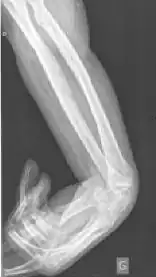

Contracturen kunnen ook het gevolg zijn van ischemie (tekort aan bloedtoevoer), wat leidt tot het afsterven van spierweefsel, zoals bij de contractuur van Volkmann. Wondcontracturen worden veroorzaakt door overmatige accumulatie van myofibroblasten en matrixmetalloproteases in wondranden (brandwonden en littekens) na letsel.[3]